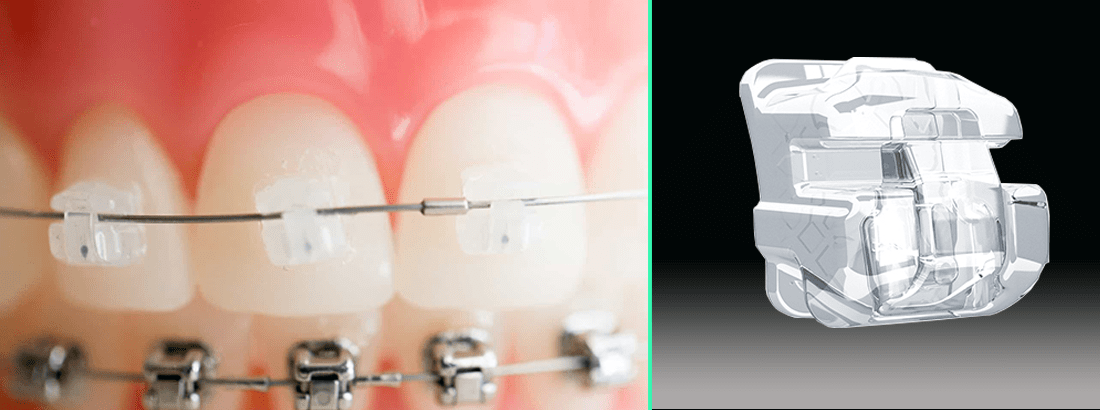

Самолигирующие сапфировые брекеты Damon Clear: особенности и фотографии